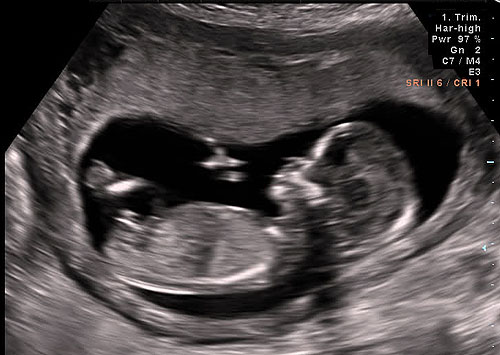

Read MorePrenatal Protection?

What does Missouri law say about unborn children? According to the Missouri Constitution – Article I, Section 2 states that all persons have a natural right to life, liberty, the pursuit of happiness, and the enjoyment of their own industry. Missouri statutes (RSMo 1.205) explicitly state life begins at conception: 1.205. Life begins at conception —…